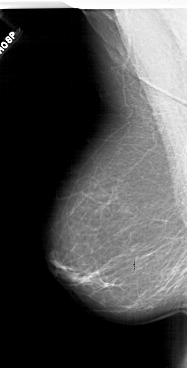

A_1718_1.RIGHT_MLO

LEFT_MLO LINES 6241 PIXELS_PER_LINE 3166 BITS_PER_PIXEL 12 RESOLUTION 43.5 NON_OVERLAY